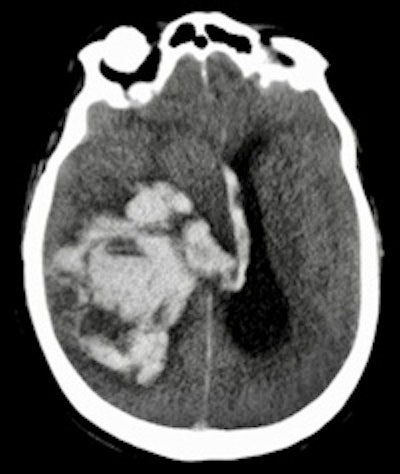

Postmortem imaging is performed at Erasmus University Medical Center.The primary outcome measure was performance of minimally invasive autopsy and conventional autopsy in establishing immediate cause of death, as compared with consensus immediate cause of death. The group also compared the diagnostic yield of the minimally invasive technique with conventional autopsy for all, major, and grouped major diagnoses; frequency of clinically unsuspected findings; and percentage of answered clinical questions.

| Cerebral pathology | 10 (11%) |